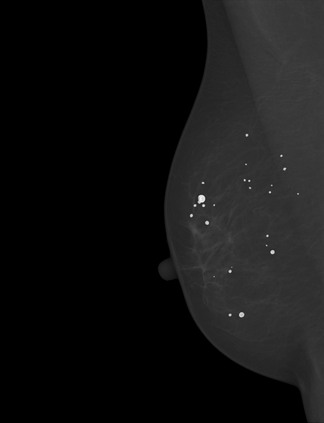

Breast cancer is the most widespread neoplasm among women and early detection of this disease is critical. Deep learning techniques have become of great interest to improve diagnostic performance. Nonetheless, discriminating between malignant and benign masses from whole mammograms remains challenging due to them being almost identical to an untrained eye and the region of interest (ROI) occupying a minuscule portion of the entire image. In this paper, we propose a framework, parameterized hypercomplex attention maps (PHAM), to overcome these problems. Specifically, we deploy an augmentation step based on computing attention maps. Then, the attention maps are used to condition the classification step by constructing a multi-dimensional input comprised of the original breast cancer image and the corresponding attention map. In this step, a parameterized hypercomplex neural network (PHNN) is employed to perform breast cancer classification. The framework offers two main advantages. First, attention maps provide critical information regarding the ROI and allow the neural model to concentrate on it. Second, the hypercomplex architecture has the ability to model local relations between input dimensions thanks to hypercomplex algebra rules, thus properly exploiting the information provided by the attention map. We demonstrate the efficacy of the proposed framework on both mammography images as well as histopathological ones, surpassing attention-based state-of-the-art networks and the real-valued counterpart of our method. The code of our work is available at https://github.com/elelo22/AttentionBCS.